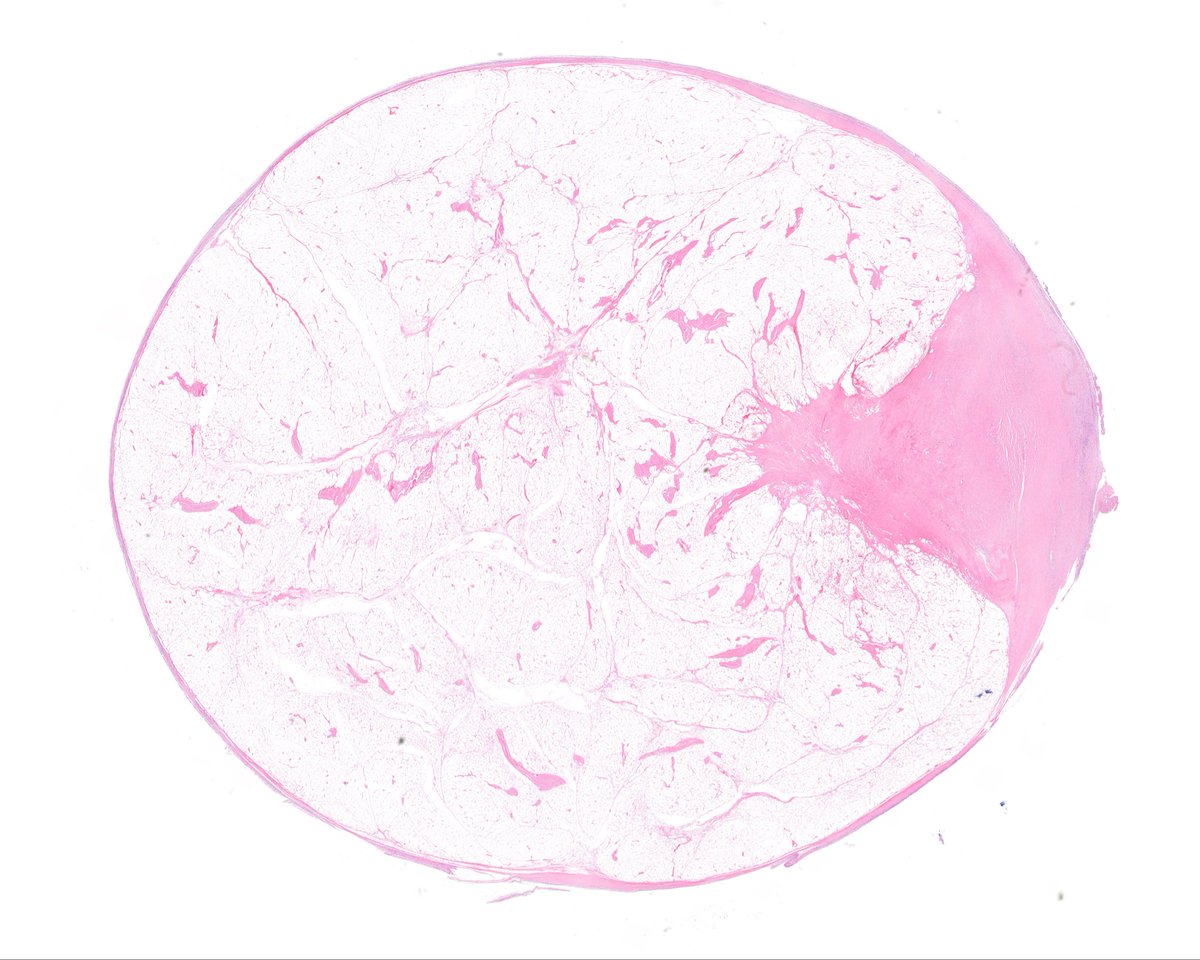

Does This Imaging Make Me Look NFATC2? The Value of... : The American Journal of Surgical Pathology journals.lww.com/ajsp/abstract/…

Does this imaging make me look NFATC2?